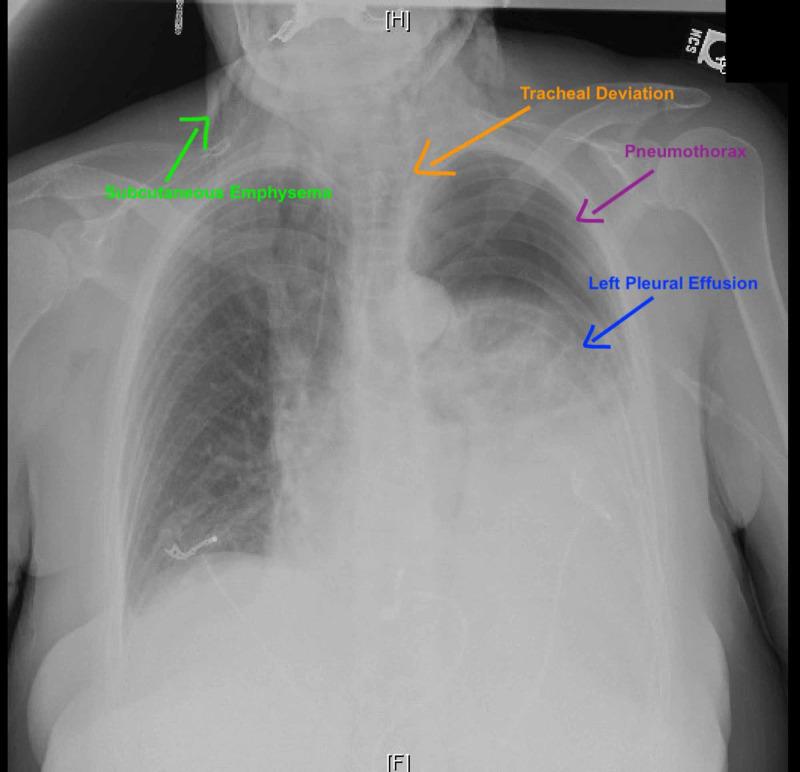

The authors present a case of a patient who used Kambo frog poison for body cleansing that induced severe vomiting and led to esophageal rupture followed by tension pneumothorax and septic shock. Kambo is the waxy substance secreted by the nocturnal giant tree frog . Kambo, which is poisonous, is commonly believed in South America to have cleansing and healing properties. As alternative medicine becomes more common, and as more tourists frequent our hospitals, knowledge of these types of ritual related exposures is important for the practicing emergency physician to be aware of.

作者报告了一例患者,该患者使用坎波蛙毒进行身体清洁,引发了严重呕吐,导致食管破裂,随后出现张力性气胸和感染性休克。坎波是夜行性巨树蛙分泌的蜡状物质。坎波有毒,在南美洲通常被认为具有清洁和治疗功效。随着替代医学越来越普遍,以及越来越多游客前往我们的医院就诊,了解这些与仪式相关的接触类型对于执业急诊医生来说非常重要。